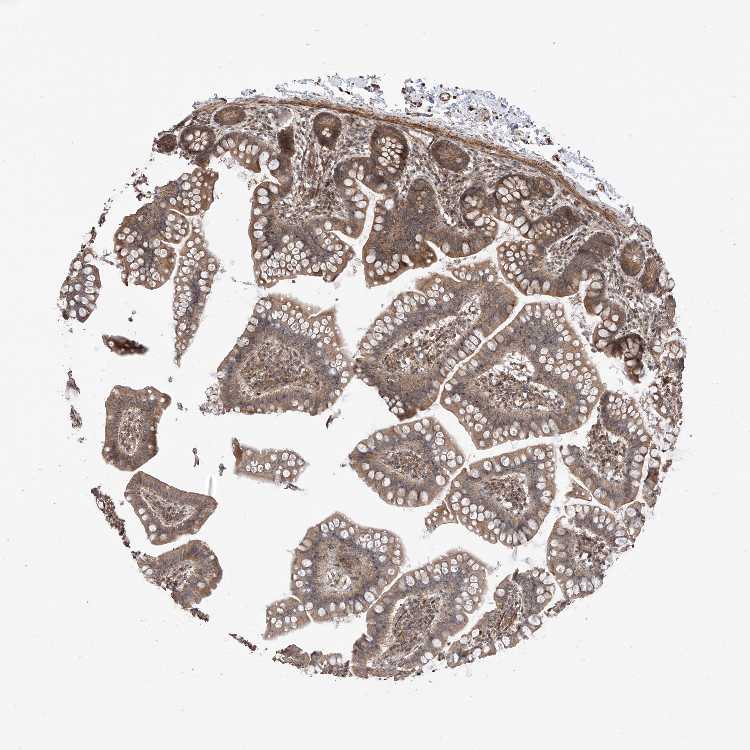

SMALL INTESTINE - Antibody stainingi

Antibody staining in the annotated cell types in the current human tissue is reported as not detected, low, medium, or high, based on conventional immunohistochemistry profiling in selected tissues. This score is based on the combination of the staining intensity and fraction of stained cells.

Each image is clickable and will lead to virtual microscopy that enables deeper exploration of all samples and also displays staining intensity scores, fraction scores and subcellular localization as well as patient and tissue information for each sample.

Antibody HPA031804

Glandular cells Medium